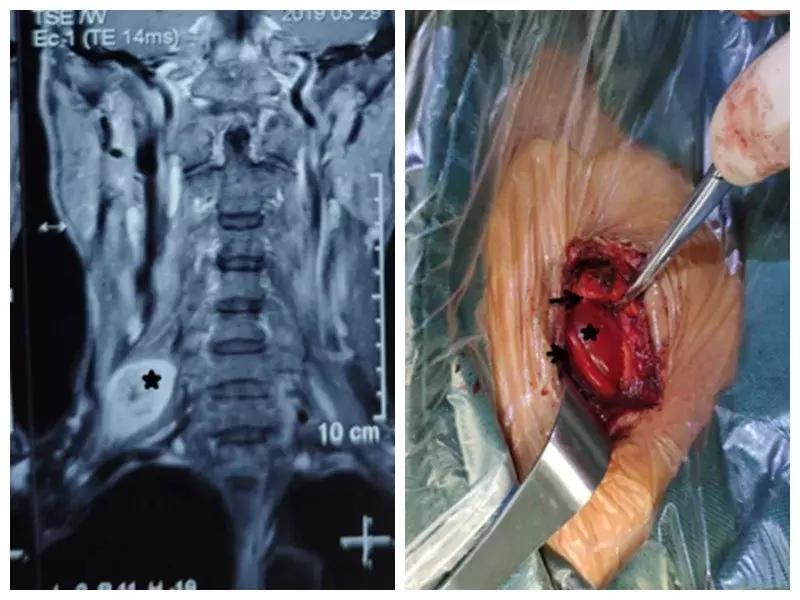

家住户县的王师傅一年前无意中发现右颈部长了一个“包”,当时并未在意,但是他发现这个“包”逐渐增大,并且伴有压痛,按压这个“包”时还可引起右胳膊疼痛,在当地医院就诊,未见好转,在我市某三甲医院检查及包块穿刺活检示右侧颈部神经鞘瘤,医生告诉他可以手术切除,但是风险很大。王师傅慕名来到西安市中心医院骨一科就诊,严少荣主任接诊后立即安排住院治疗,并安排由西安市手外科常委王涛主任医师及主治医师张磊组成治疗小组。积极进行术前检查,发现右颈部肿瘤有3×3×3 cm大小活动性差的肿瘤。并有触电样感觉向肢体放射。经过制定缜密手术方案,严主任细心耐心告知患者手术的风险性,并安排术中神经电生理监测,提高手术安全性,由王涛主任医师、张磊主治医师和麻醉医师李楠及手术护士组成手术团队,在全麻下行右侧颈部神经鞘瘤切除术,术中发现此神经鞘膜瘤巨大,位于臂丛神经上干并包饶颈5.6神经,与周围组织黏连严重,由于该肿瘤起源于神经根纤维许旺氏细胞,遂着肿瘤不断生长,将神经干内正常神经纤维挤向肿瘤四周,包含在神经外膜内形成肿瘤的“包膜”呈鱼肉样。王涛主任医师在仔细保护神经的情况下采用“层层剥离挤出法”将肿瘤取除,避免了误将含正常神经纤维的“包膜”随肿瘤一起切除,造成神经干损伤及缺失,从而造成上肢功能的不可逆障碍的悲剧。术后经过主管护士解妍及全体医护人员的精心治疗护理,王师傅原有神经压迫症状消失,无任何感觉运动异常,术后再次病检符合神经鞘瘤。王师傅满意出院。

通过此例罕见臂丛神经上干神经鞘瘤病人治疗,标志着我科在高位臂丛神经干手术达到一个新高度。